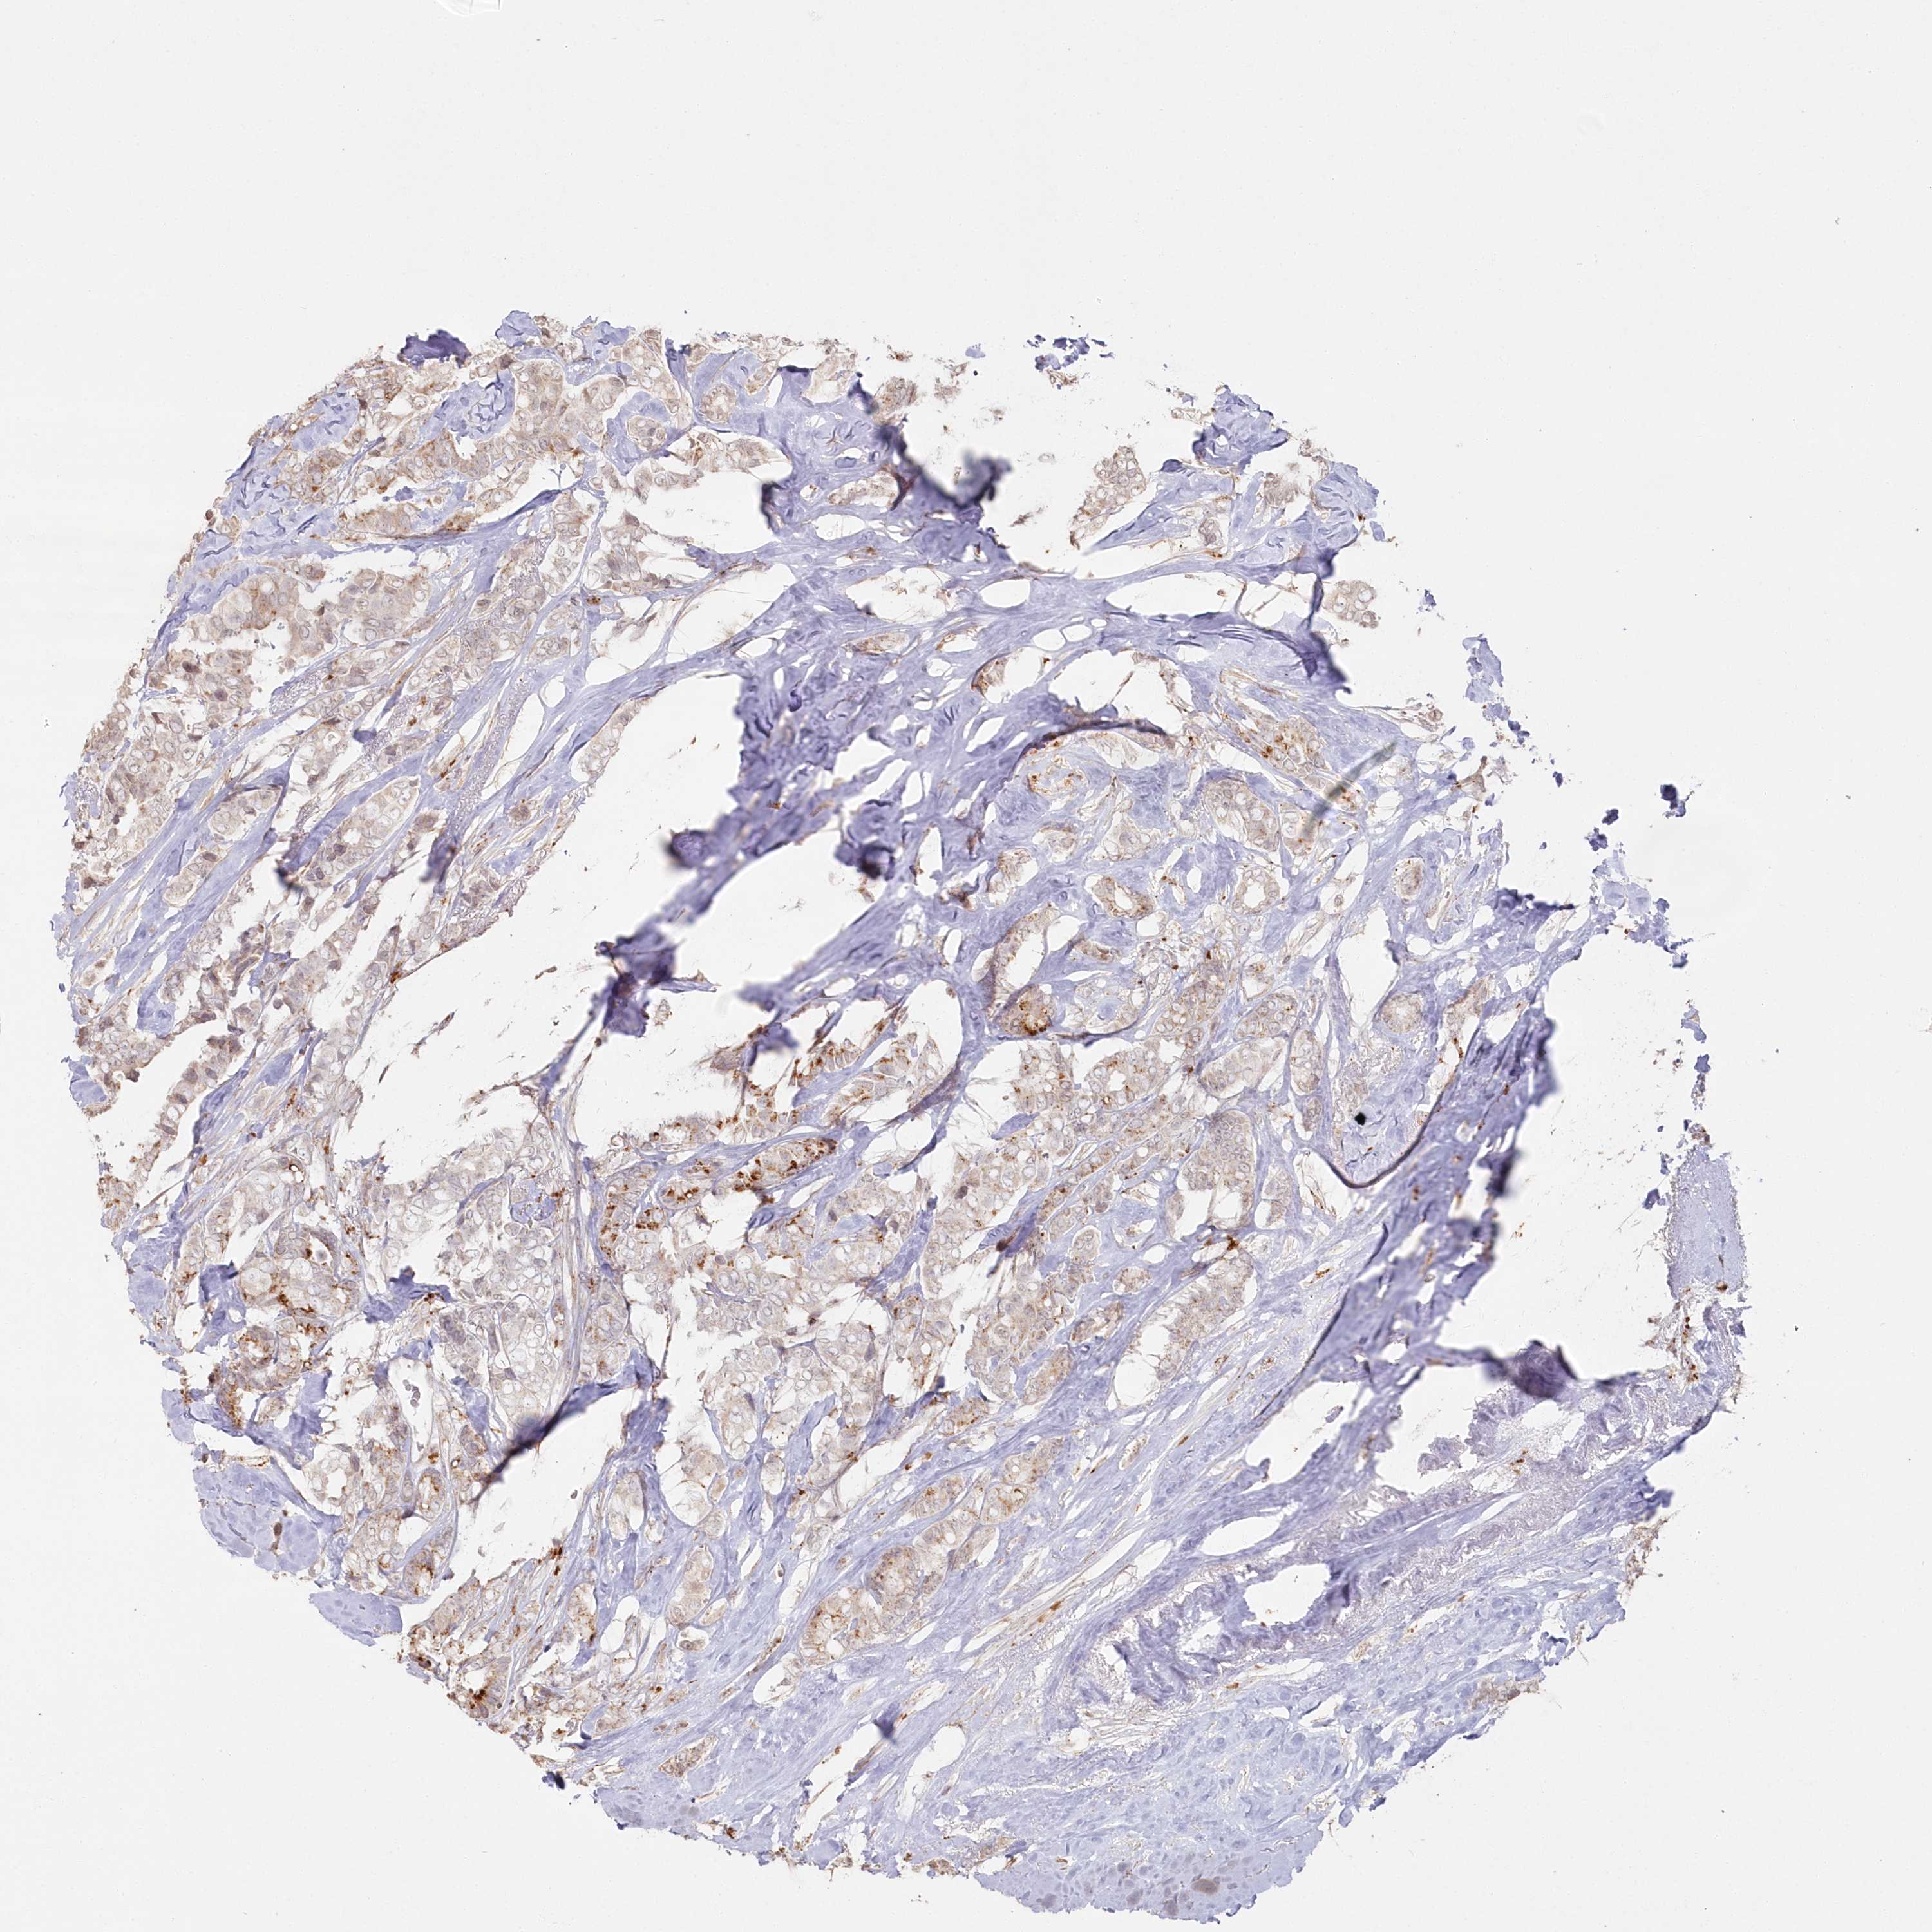

CANCER BREAST CANCER Show tissue menu

BRCA TCGA BRCA VALIDATION PROTEIN EXPRESSION